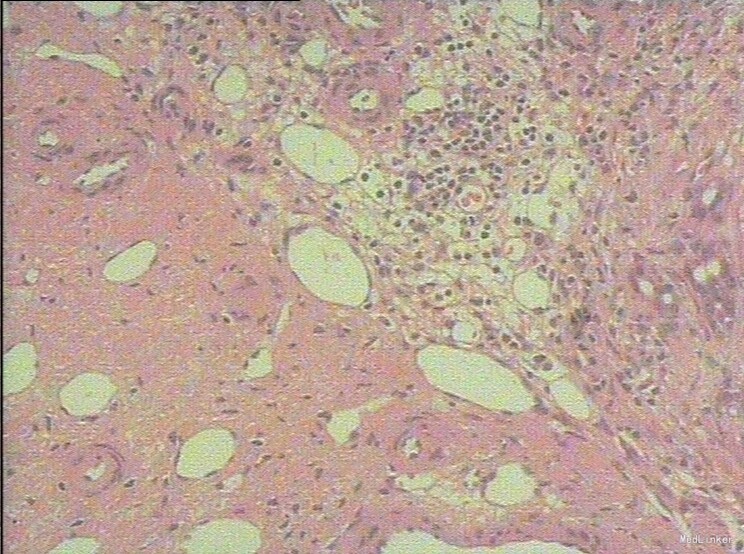

随访:术后病理示:(右肝肿物)送检肝组织部分呈结节状增生,结节间见粗细不等的纤维间隔,其内见血管增生,少量淋巴细胞及浆细胞浸润,符合肝局灶性结节状增生(FNH)。 讨论:肝局灶性结节增生(FNH)是肝内第二常见良性肿瘤,一般无临床症状,影像学表现,MRI上T1WI和T2WI与周围肝实质信号相近,增强扫描动脉期明显强化,若存在中央瘢痕,则中央瘢痕不强化,门脉期及静脉期强化程度减退,中央瘢痕则呈延迟强化。FNH需与肝癌和肝腺瘤鉴别,本例即误诊为肝癌,若存在中央瘢痕,则诊断较容易。